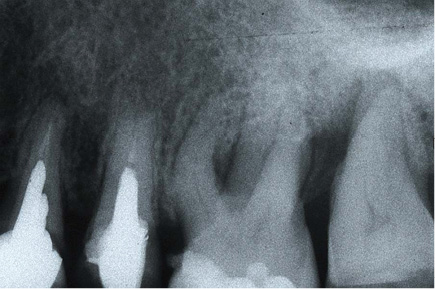

At the time of the examination, 10 (90.9%) ECs were in function in 10 patients. One EC had been lost after 12 years and 9 months due to periodontal disease in tooth #26. No restoration had loosened. Neither secondary caries nor radiographic failures were observed in the 10 PETT in function (Figs. 1a,1d; 2c; 3c,3d; 4c).

Fig. 3c Final control of endodontic treatment.

Fig. 3d X-ray control after 18 years.